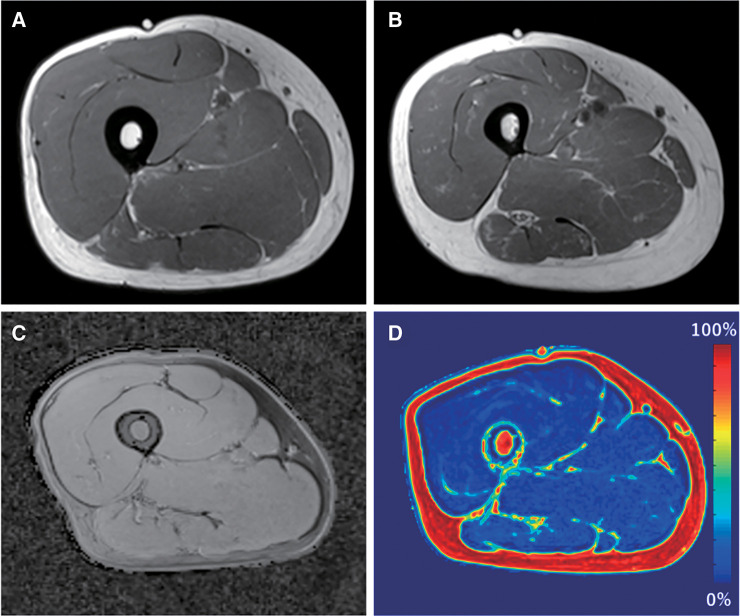

A decline in muscle strength is a key factor responsible for physical dysfunction in older individuals. Both loss of muscle quantity and quality are associated with muscle strength decline. While the gold standard method for evaluating muscle mass and quality is magnetic resonance imaging, it is not suitable for clinical settings because of the measurement and analysis costs. Bioelectrical impedance analysis (BIA) and B-mode ultrasonography are clinically useful alternatives for skeletal muscle assessment owing to their feasibility and noninvasiveness. The recent advancements in the techniques for BIA and ultrasonography have improved their accuracy in assessing skeletal muscle quantity and quality, making them useful in detecting age-related and disease-specific alterations. This review comprehensively analyzes the advantages of using BIA and ultrasound imaging for assessing skeletal muscle quantity and quality and detecting muscle degeneration. We summarize the recent findings regarding age-related changes in muscle characteristics and the associations of muscle degeneration with physical dysfunction in patients with knee osteoarthritis. Furthermore, we discuss the clinical application of skeletal muscle assessment using BIA and ultrasound for evaluating training effects and exercise prescription.